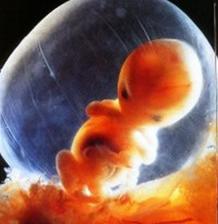

29.4. druhá KO u dr 7+3, 12,3mm a srdíčko bije

23.5. pro průkazku + odběr krve + utz 11+0 mimisek 4,2cm